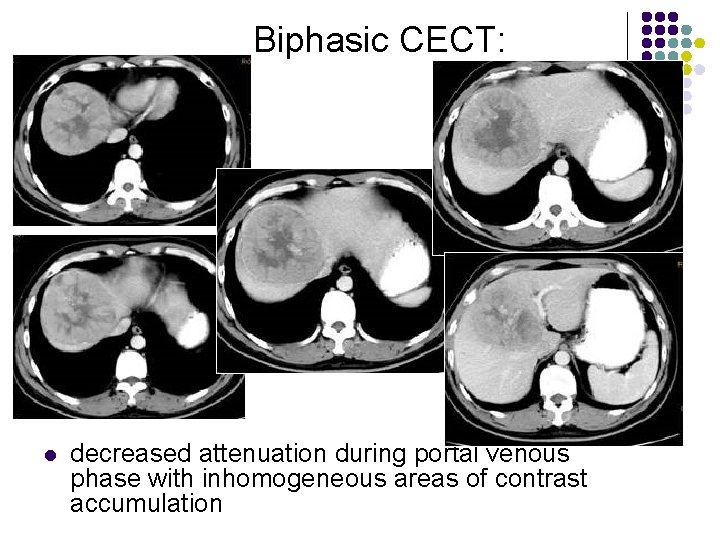

Biphasic CECT: l l l enhancement during hepatic arterial phase (80%) decreased attenuation during portal venous phase with inhomogeneous areas of contrast accumulation isodensity on delayed scans (10%) thin contrast-enhancing capsule (50%) due to rapid washout wedge-shaped areas of decreased attenuation (segmental/lobar perfusion defects due portal vein occlusion by tumor thrombus)

Biphasic CECT: l decreased attenuation during portal venous phase with inhomogeneous areas of contrast accumulation

Biphasic CECT: l decreased attenuation during portal venous phase with inhomogeneous areas of contrast accumulation